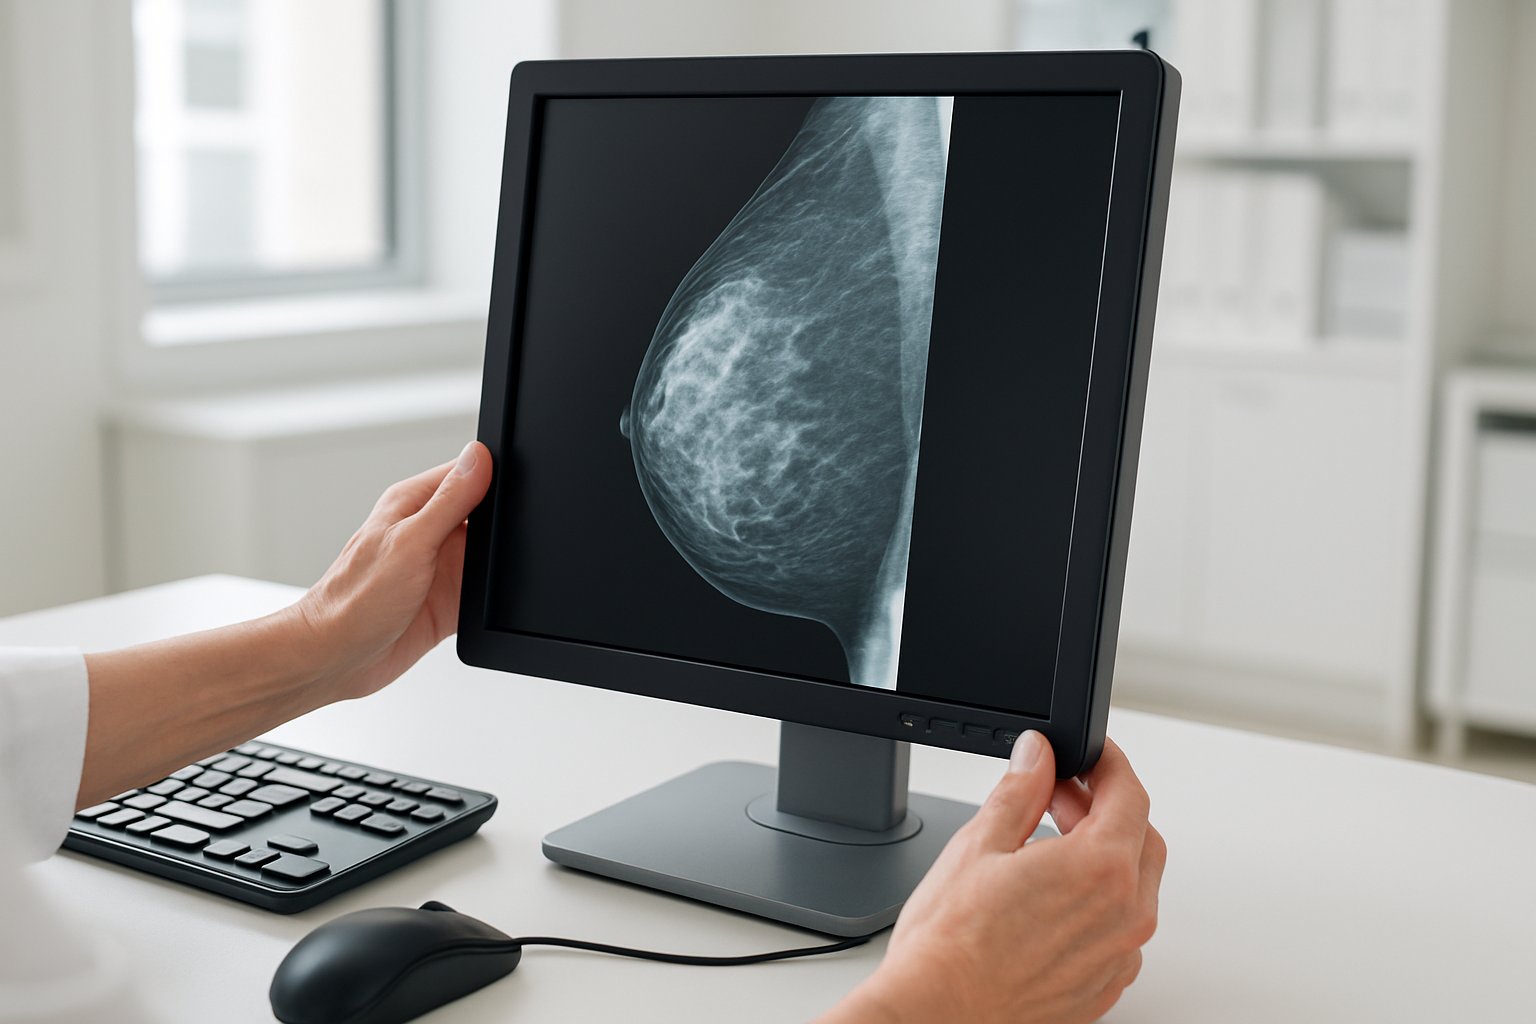

Breast Imaging AI powers Novarad MammoIQ launch

The company claims its framework embeds Breast Imaging AI to accelerate reads while meeting stringent U.S. regulations. Meanwhile, clinicians face mounting pressures from larger datasets, denser tomosynthesis stacks, and tightening reimbursement. This article examines how MammoIQ positions itself, the market forces driving adoption, and the potential hurdles ahead.

MammoIQ bundles multiple capabilities under one interface. Radiologists can toggle between 2D mammography and 3D tomosynthesis slices while simultaneously displaying ultrasound, MRI, or PET data. Furthermore, contralateral magnification sync and longitudinal region tracking help monitor subtle interval changes. Novarad promises ultra-fast preprocessing with local caching that minimizes wait times.

Embedded algorithms provide Breast Imaging AI support for quality assurance and cancer screening triage. The vendor’s historic partnerships with CureMetrix and Ikonopedia suggest FDA-cleared modules may underpin early releases. Additionally, volumetric density estimation and automated BI-RADS abstraction arrive pre-configured. David Grandpre, Vice President of Product at Novarad, said, “This framework addresses critical regulatory requirements while providing an end-to-end, integrated platform for mammography.”